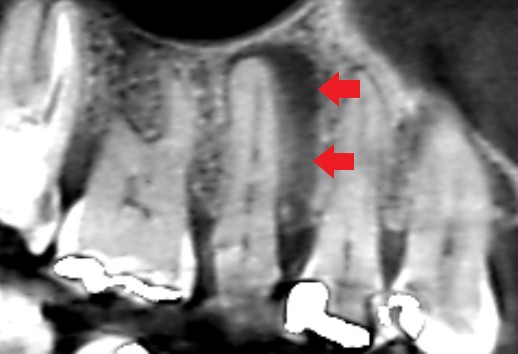

根管治療6ヶ月後のCT画像です。根の横にみられた長い影が消失し、歯槽骨が再生しています。

最初にみられた長い影は、歯根破折ではなく根尖病変が原因だったケースです。歯根破折が疑えるようなケースでも、歯科用顕微鏡で精密にチェックすることが重要です。そうすれば、誤診せず抜歯を免れる可能性があります。